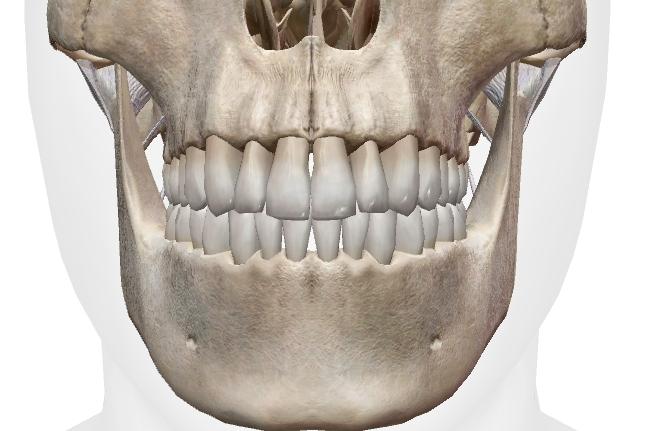

線維性関節(線維性連結)

コラーゲンなどを成分とする強靭な繊維の束によって連結されている部位。

頭蓋の 縫合、上下顎骨と歯の釘植(ていしょく)がそれにあたります。

歯周病菌などに侵されたら歯は抜けますが、それ以外では当然動かない(動かせない)不動関節です。